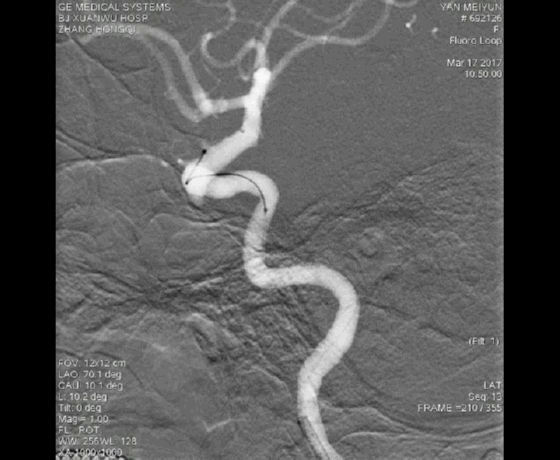

病例三

A1起始段动脉瘤,微导管成袢逆行到位